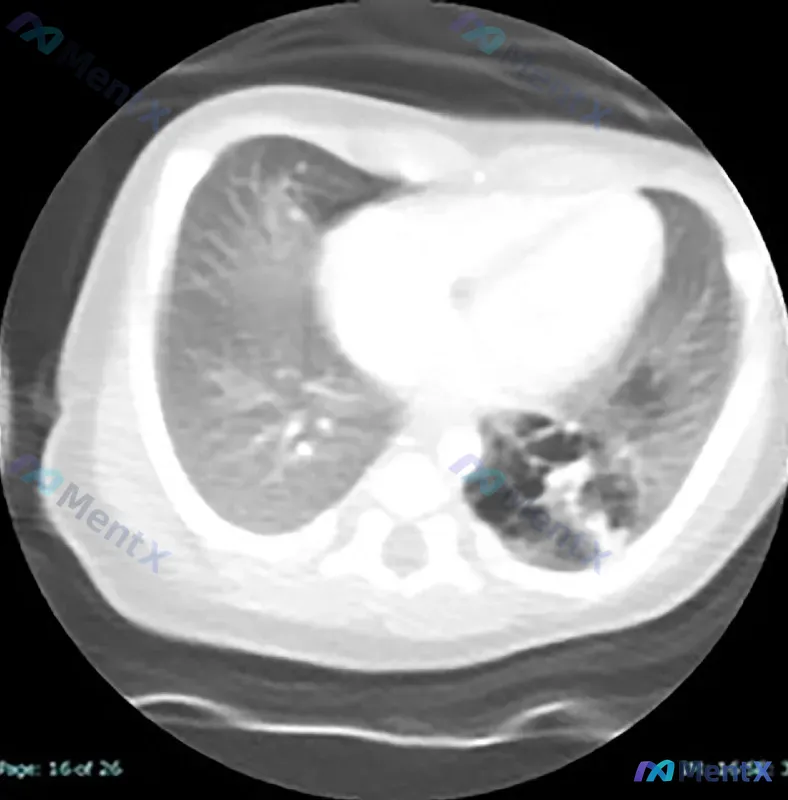

出生47天新生儿左下叶囊性含气病变,第一反应会考虑什么?

整理了一个病例的核心信息,先不把结论放全,看看第一反应会不会有明显分化: - 基本情况:出生后第47天的新生儿 - 影像表现:轴位CT血管造影显示左下叶以囊性含气为主的混合性病变,局部有实变影与透亮区混合,可见肺结构扭曲 - 暂未提供:产前超声结果、出生后早期影像、症状史、感染指标 这份病例如果只看...